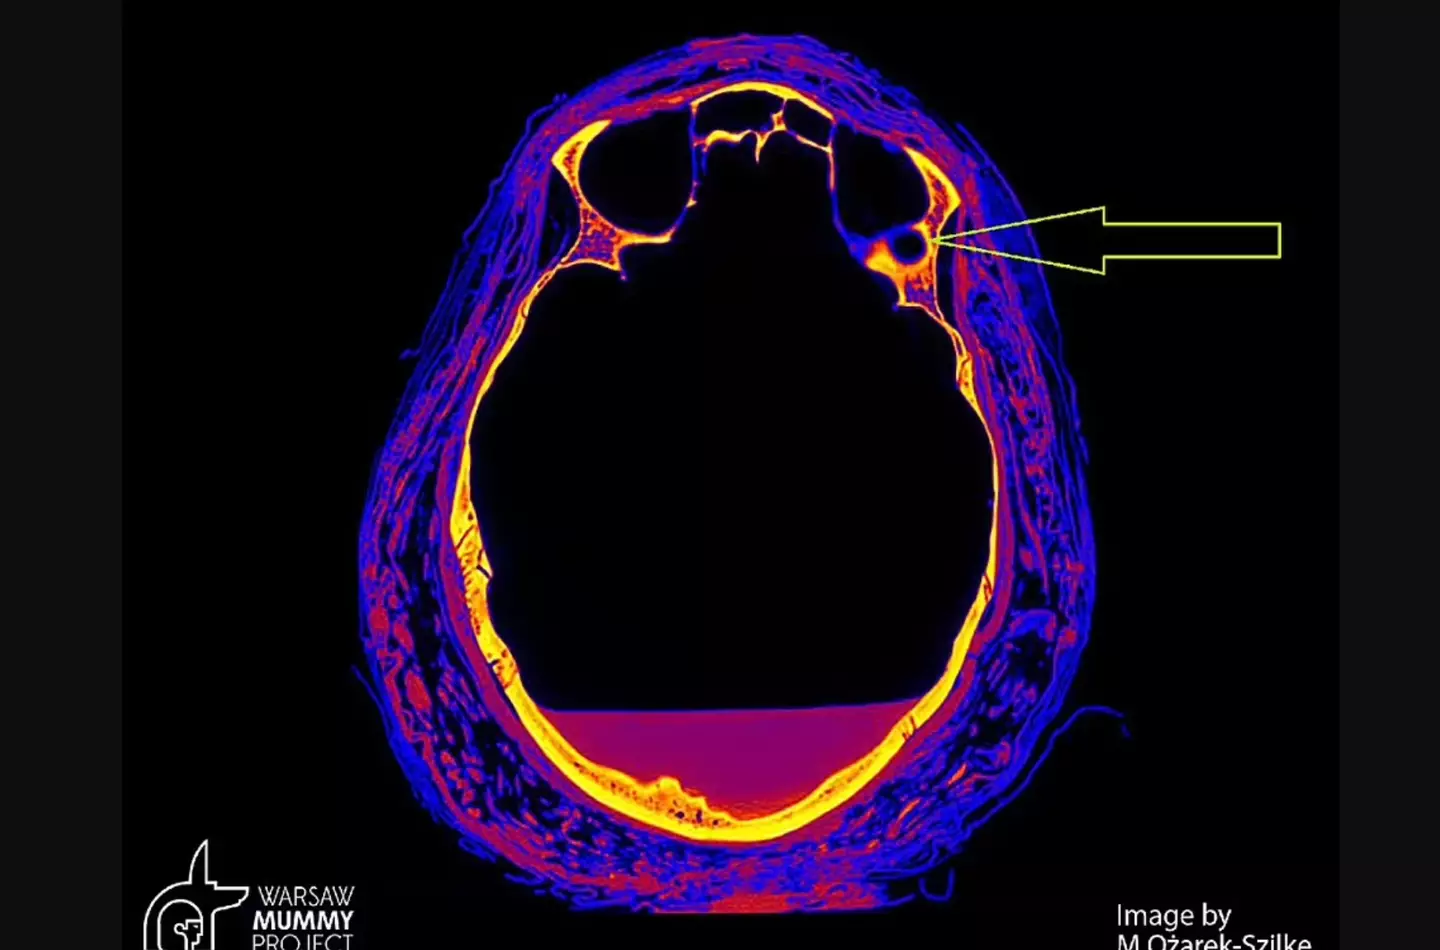

The scan revealed unusual marks inside the skull, similar to those that are found in patients with nasopharyngeal cancer, leading researchers to believe this is what the woman died of.

Scan images from Warsaw Mummy Project show lesions on the skull, which were most likely caused by a tumour, as well as various defects in parts of the bones that are not typically present in mummification.

Professor Rafał Stec from the Medical University of Warsaw's Department of Oncology, said: “We have unusual changes in the nasopharyngeal bones, which, according to the mummy experts, are not typical of the mummification process.

“Secondly, the opinions of radiologists based on computed tomography indicate the possibility of tumour changes in the bones.”